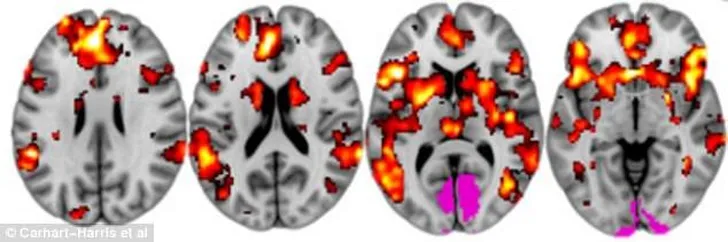

Voor het onderzoek werd de hersenactiviteit van veertig mensen gemeten, waarvan de ene helft echte LSD en de andere helft een placebo kreeg toegediend. Op de scans is zichtbaar dat mensen die hallucineren door de drug daadwerkelijk 'zien' met meerdere delen van hun hersenen. Een soort derde oog, dus, waarmee je bijvoorbeeld geluiden kan zien.

Scans van de mensen met een placebo